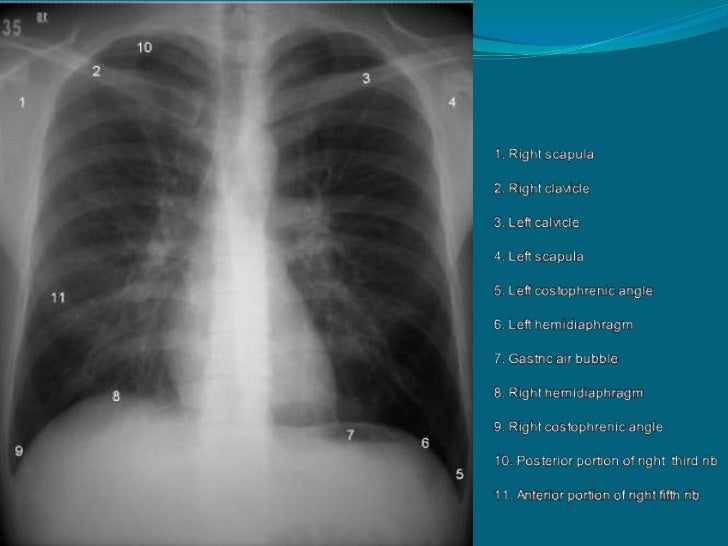

Fibrosis Pulmonar Rx / Patrones Radiograficos Pulmonares Rx Tcar / Pulmonary fibrosis information including symptoms, diagnosis, misdiagnosis, treatment, causes, patient stories, videos, forums, prevention, and prognosis.

Fibrosis Pulmonar Rx / Patrones Radiograficos Pulmonares Rx Tcar / Pulmonary fibrosis information including symptoms, diagnosis, misdiagnosis, treatment, causes, patient stories, videos, forums, prevention, and prognosis.. The idiopathic pulmonary fibrosis honeycomb cyst contains a mucocilary pseudostratified epithelium. Acompaña a una fibrosis pulmonar secundaria a lesiones inflamatorias crónicas, tales como la tuberculosis. Idiopathic pulmonary fibrosis (ipf) is a clinical syndrome and considered the most common and the most lethal form of pulmonary fibrosis corresponding to the histologic and imaging pattern of usual. Sections interstitial (nonidiopathic) pulmonary fibrosis. Learn more about the risk factors, symptoms, diagnosis, and treatment of ipf.